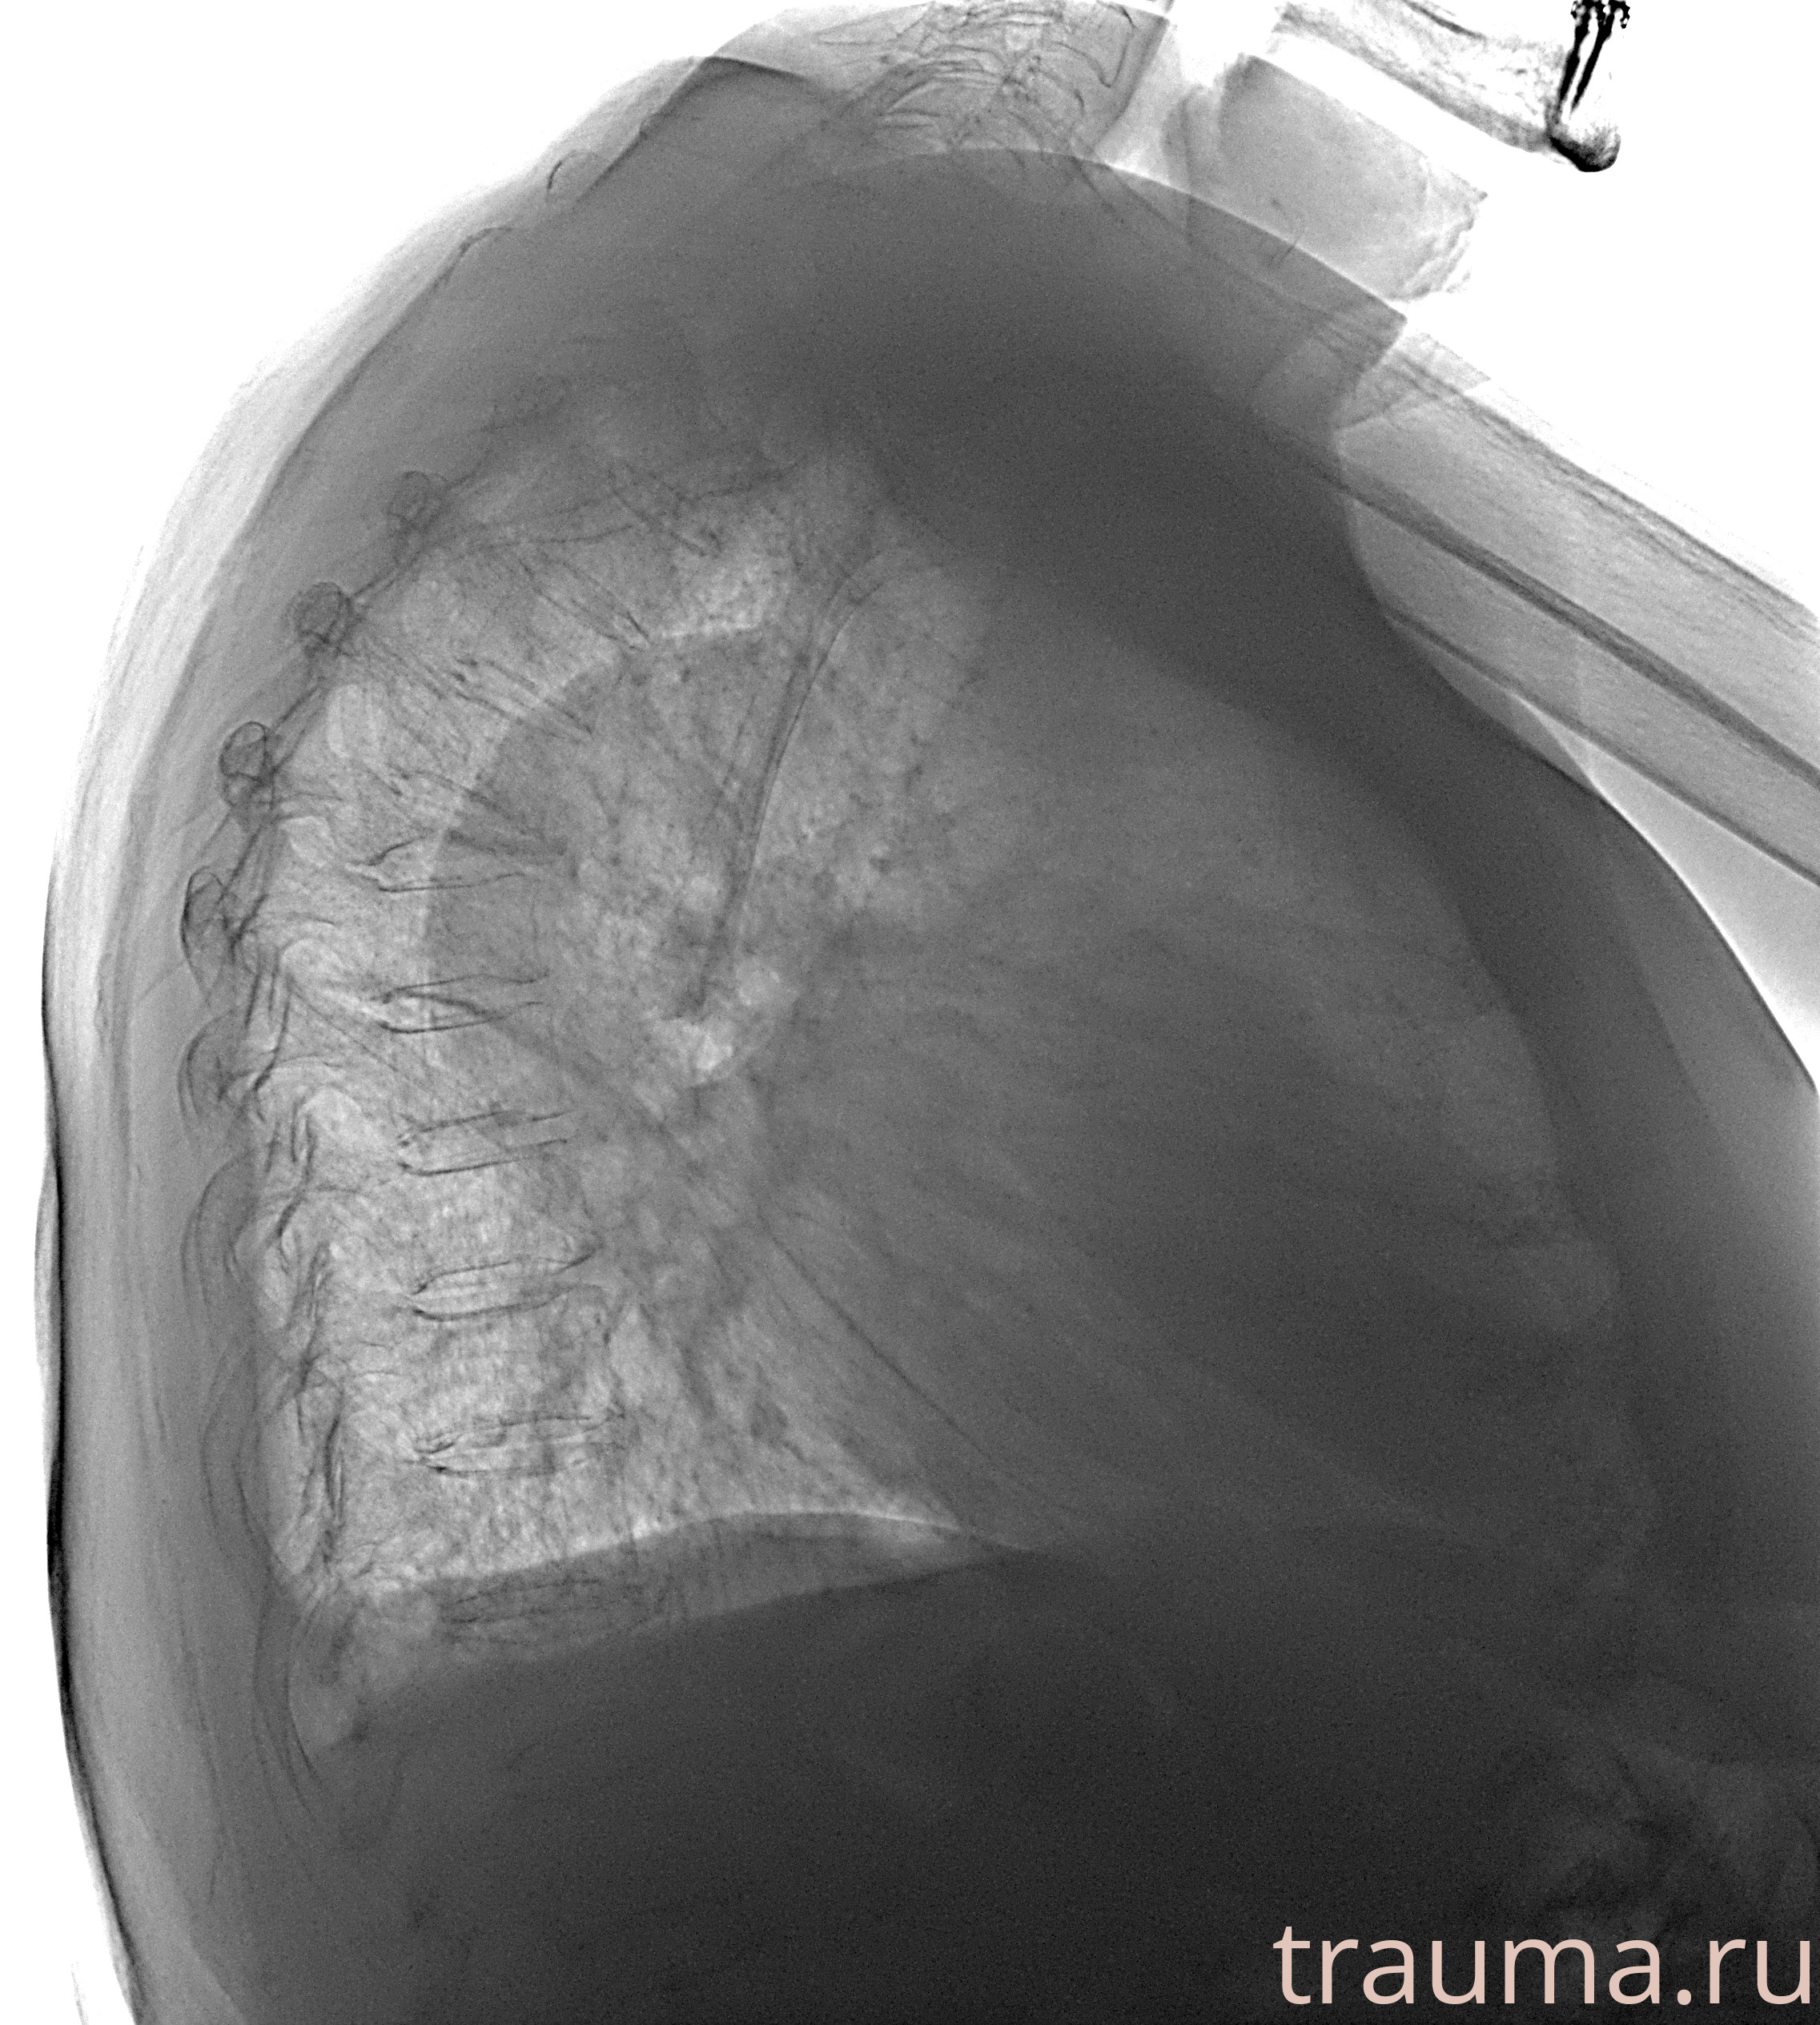

Рентген на дому: по вашему адресу приезжает врач-рентгенолог, травматолог-ортопед с мобильным рентгеновским аппаратом, проводит диагностику травмы или заболевания, делает необходимые рентгенограммы, дает рекомендации по дальнейшему лечению. Получить качественные снимки в домашних условиях возможно благодаря уникальной методике, разработанной МосРентген Центром для института  Склифосовского